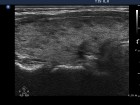

Follow-up examinations (rows from 1st to 8th):

30 |

16.7 |

Nothing |

0.06 |

41.5 |

15 |

20 mg methimazole |